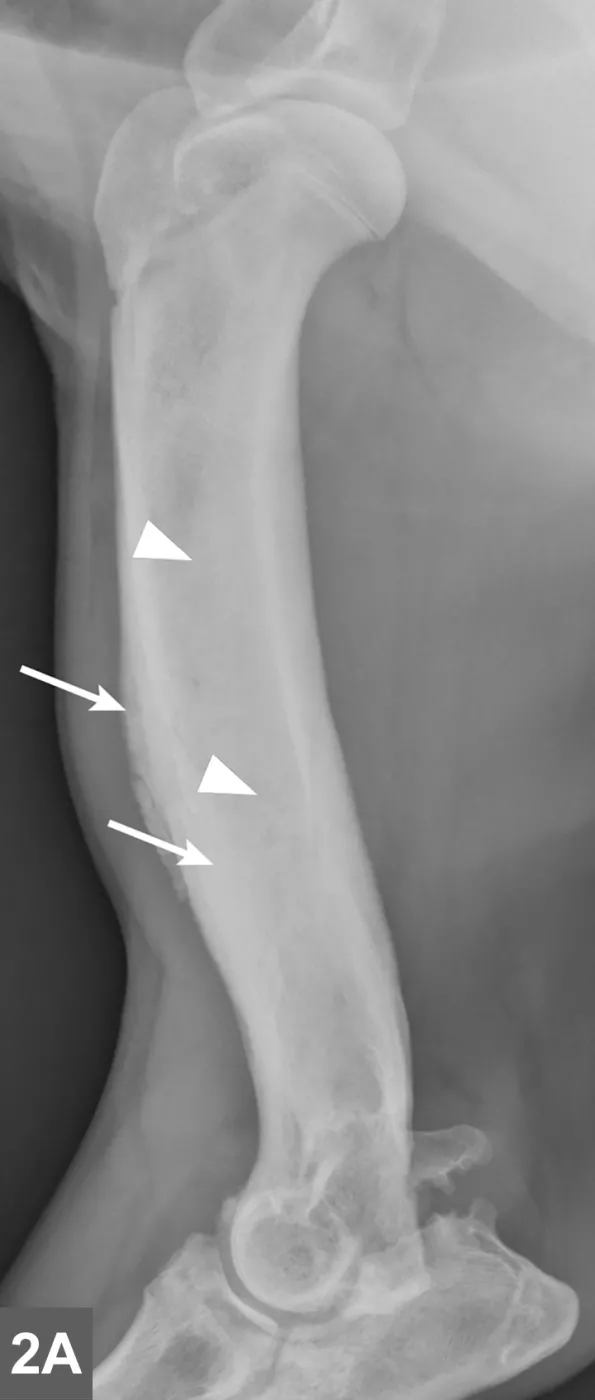

FIGURE 1A

Lateral radiographic projections of the femur (A) and ulna (B, next slide) in dogs with early signs of panosteitis. Note the radiolucency around the nutrient foramen (arrows) and increased opacity within the medullary canal (arrowheads) in both cases.